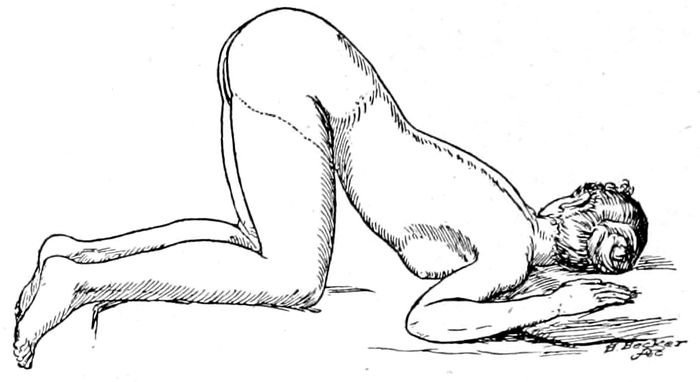

| 101. |

The knee-chest posture |

236 |

| |

| 16102. |

The exaggerated lithotomy position obtained with a sheet sling |

237 |

| |

| 103. |

The improvised Trendelenburg position |

237 |

| |

| 104. |

The dorsal position with stirrups |

238 |

| |

| 105. |

Dorsal position across the bed |

239 |

| |

| 106. |

Flexed dorsal position with feet on the table |

240 |

| |

| 107. |

The Sims position |

241 |